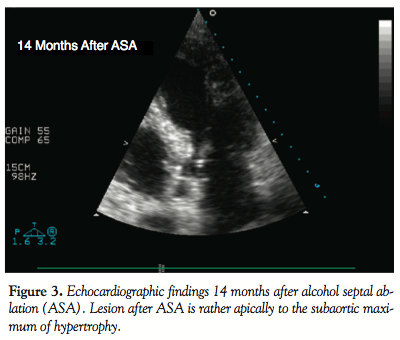

However, 1 year later, the patient presented with a new worsening of dyspnea and manifestation of angina with slow progression to NYHA class 3 and CCS class 2 again. Transthoracic echocardiography performed 14 months after ASA revealed significant subaortic obstruction with SAM. Based on CW Doppler, the subaortic gradient was 26 mm Hg at rest, but it increased up to 200 mm Hg after nitrate provocation. The ASA lesion was smaller and located slightly distally to the subaortic maximum (Figure 3). The location of the septal bulge with regard to the arterial supply didn’t allow performance of a new ASA and performance of surgical myectomy was therefore discussed with the patient. However, the patient refused surgical treatment and therefore ERASH was offered to the patient as an option. After providing detailed information about the procedure, its potential risks, and possible complications, the patient gave and signed informed consent.